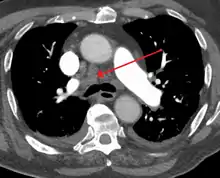

Widened mediastinum | |

Other names | Mediastinal widening |

![]() | |

Widened mediastinum in a patient with achalasia |

Widened mediastinum/mediastinal widening is where the mediastinum has a width greater than 6 cm on an upright PA chest X-ray or 8 cm on supine AP chest film.[11]

A widened mediastinum can be indicative of several pathologies:[12][13]

- aortic aneurysm[14]

- aortic dissection[15]

- aortic unfolding

- aortic rupture

- hilar lymphadenopathy

- anthrax inhalation - a widened mediastinum was found in 7 of the first 10 victims infected by anthrax (Bacillus anthracis) in 2001.[16]

- esophageal rupture - presents usually with pneumomediastinum and pleural effusion. It is diagnosed with water-soluble swallowed contrast.

- mediastinal mass

- mediastinitis

- cardiac tamponade[17]

- pericardial effusion

- thoracic vertebrae fractures in trauma patients.